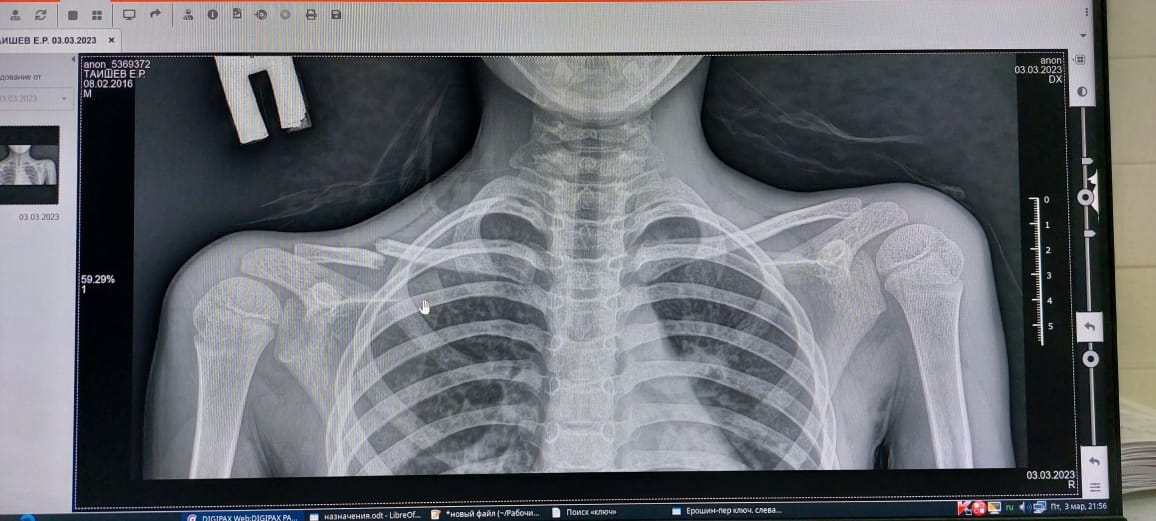

Первое фото сразу после травмы, второе - вчерашний рентген через 2,5 мес после травмы. Ключицу ломал сын на тренировке.